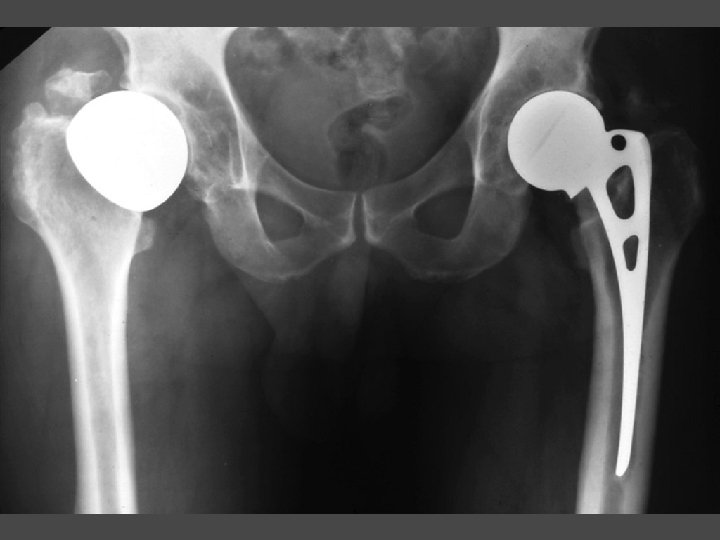

THA OA vs ON • Two matched groups of THA (cemented Charnley) • 94 hips each • Matched for age, sex, surgeon, approach, and prosthesis • 70 m 118 f • 58 yrs (30 -79) Follow-up 17. 8 yrs (10 -25)

THA OA vs ON Results Revision rates ON 18% OA 19% <50 yrs: ON revision rate (p<. 005) Acetabular loosening no different Femoral loosening higher in ON (p<0. 05) Complications same except dislocation higher in ON (p<. 05)